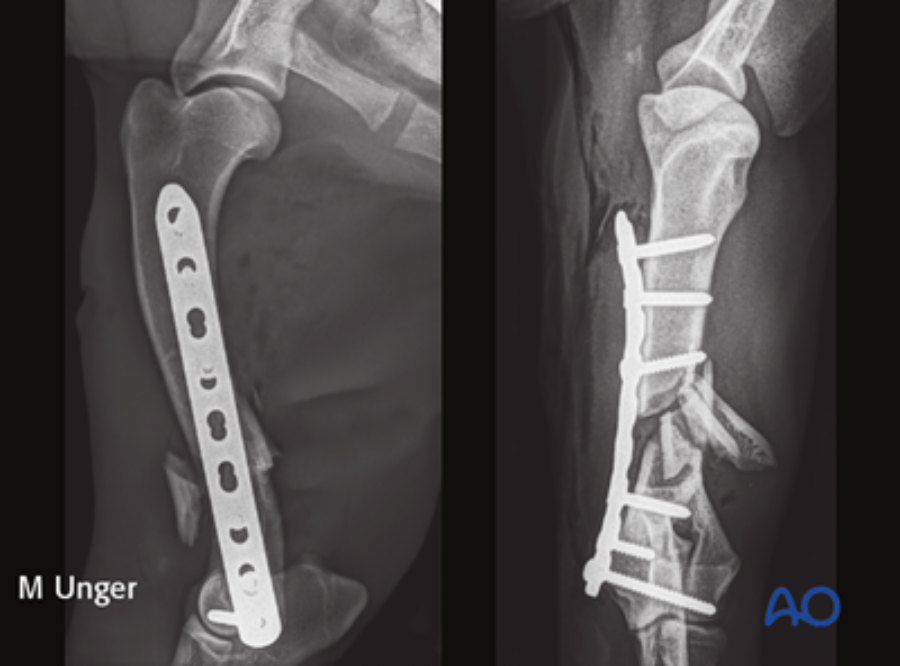

The module on this anatomical area was authored by Martin Unger (Germany). Matthew J Allen (UK) and Aldo Vezzoni (Italy) acted as editors.

This module follows the AO VET classification for long bones. It offers an in-depth description of both lateral and medial approaches, along with a detailed exploration of a minimally invasive approach for the dog humeral shaft.

It encompasses both nonsurgical and surgical management techniques, providing detailed insights into the utilization of plates, intramedullary pins, and interlocking nails for fixation. Additionally, it offers supplementary reading materials that highlight the anatomical distinctions between dogs and cats, as well as the most prevalent complications that arise during humeral shaft fracture management.